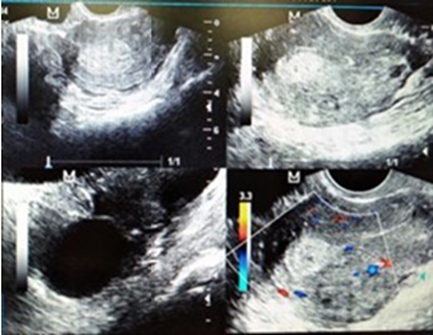

Paciente femenina de 48 años de edad, quien refiere el inicio de su enfermedad actual 6 meses después de haberle realizado una cesárea, cuando presentó edema y dolor en la cicatriz de la intervención quirúrgica, tumoración que fue aumentado de tamaño en forma progresiva. Acudió a control médico en varias oportunidades y le diagnosticaron eventración. La paciente acudió diez años después del inicio de su cuadro clínico a la consulta de la clínica de endometriosis, por aumento de tamaño de la tumoración en cicatriz posoperatoria, que se extiende a la pared abdominal anterior, dolor de moderada intensidad que ha aumentado a grave y se exacerba durante la menstruación; desde hace aproximadamente 7 meses refiere que comenzó a presentar sangramiento y expulsión de líquido amarillento por la tumoración. Entre los antecedentes personales, refirió menarquia a los 15 años, ciclo menstrual de 7/30, eumenorreica, I gesta, I cesárea, dispareunia y dolor pélvico crónico leve. No refirió otro antecedente de importancia. Al examen físico se apreció tumoración en cicatriz quirúrgica por incisión de pfannenstiel que se extendía desde la cicatriz a hipogastrio, fosa iliaca izquierda y parte inferior de flanco izquierdo, de 15 x 20 cm, multilobulada, bordes irregulares, consistencia mixta, dolor leve a moderado a la palpación y puntos secretantes de líquido citrino y sanguinolento (Figura 1). Se realizó ecografía transvaginal, donde se pudo apreciar miometrio homogéneo, imagen en pared anterior del útero, redondeada de aspecto sólido concéntrica hiperecogénica de 15,0 x 19,8 milímetros, que pudiese corresponder a un mioma intramural. En ovario derecho se observó una imagen quística unilocular, con contenido ecogénico homogéneo anecoica, sin proyecciones papilares, bordes delimitados y con dimensiones de 35,5 × 28,3 milímetros (Figura 2). Se tomó muestra para citología y biopsia de la tumoración; se pidió ecografía de partes blandas de pared abdominal, resonancia magnética y marcadores tumorales, por el cuadro de endometriosis y tumoración en ovario izquierdo.

Figura 2 Ecosonografia transvaginal donde se aprecia quiste de ovario izquierdo y mioma en pared posterior del útero.